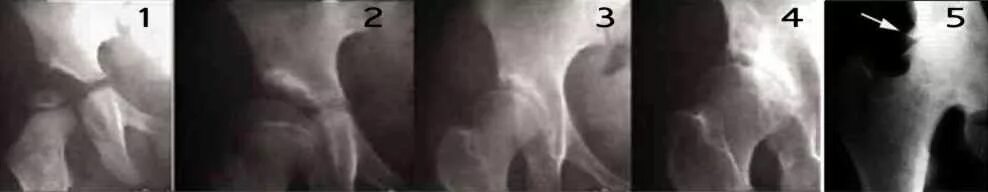

4 стадия тазобедренного сустава